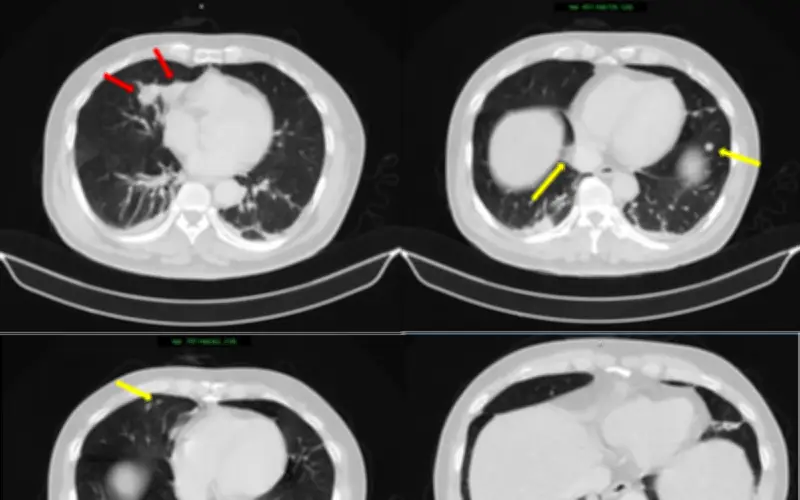

Thách thức lớn nhất trong trường hợp này là xác định bản chất của các tổn thương: đâu là khối u nguyên phát và đâu là di căn. Nếu chẩn đoán không chính xác, việc lựa chọn phương pháp điều trị có thể bị sai lệch, ảnh hưởng trực tiếp đến hiệu quả điều trị và tiên lượng của bệnh nhân. Hình ảnh từ các xét nghiệm cho thấy hai khối u bờ đa cung ở nhu mô thùy giữa phổi phải, dính vào màng phổi trung thất, kèm theo nhiều nốt đặc nhỏ rải rác ở nhu mô phổi hai bên, gợi ý tổn thương thứ phát.